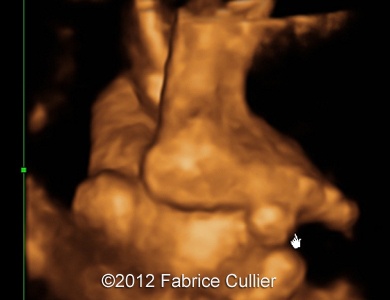

Images 8, 9: Abnormal foot with syndactyly of the four fingers, big toes positioned at right angles

6A(1)

6B(1)

Image 10, 11: 3D evaluation of the toes.

7A

7C